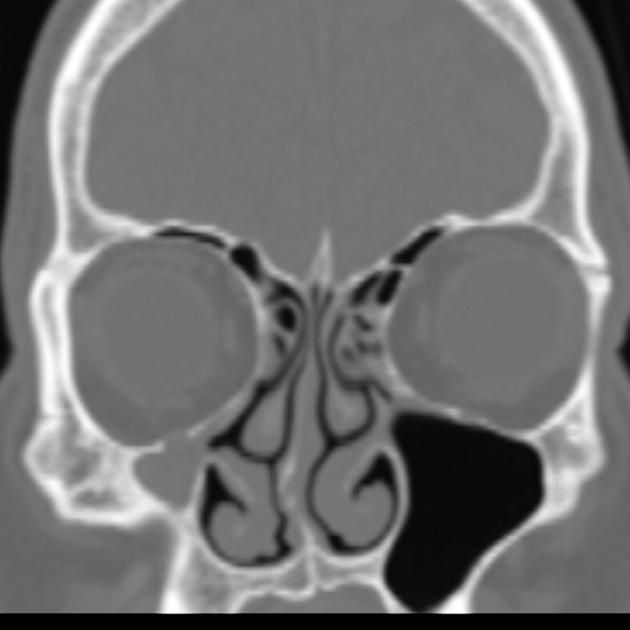

Il FUNGUS BALL:

Si tratta di una forma di sinusite cronica causata dall’accumulo di materiale fungino all’interno di un seno paranasale, più spesso il seno mascellare. Nella maggior parte dei casi, rimane confinato al seno senza invadere i tessuti circostanti.

I sintomi possono essere lievi o aspecifici e includono ostruzione nasale, secrezioni maleodoranti, dolore o senso di peso al volto, spesso da un solo lato. Talvolta la condizione viene scoperta casualmente durante esami radiologici.

La diagnosi si basa su TC dei seni paranasali, che mostra caratteristiche tipiche come aree iperdense all’interno del seno. Il trattamento è chirurgico e consiste nella rimozione del materiale fungino e nel ripristino della normale ventilazione del seno. Dopo l’intervento, la guarigione è generalmente completa senza necessità di terapia antifungina sistemica.